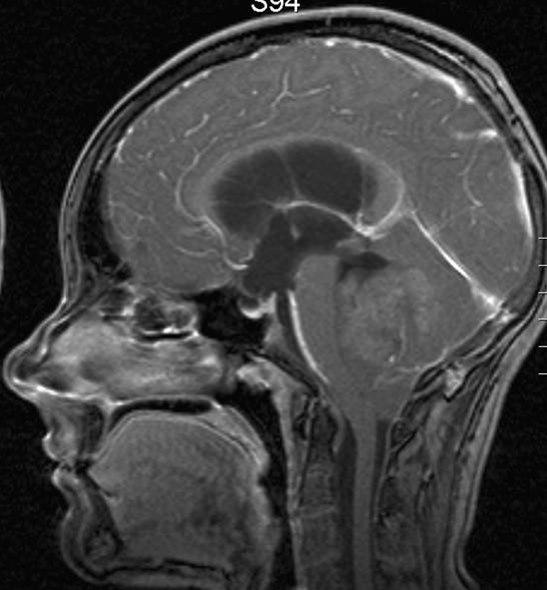

Medulloblastom, sagittalt snitt

Gjengitt med tillatelse av Radiologisk avdeling, Universitetssykehuset Nord-Norge